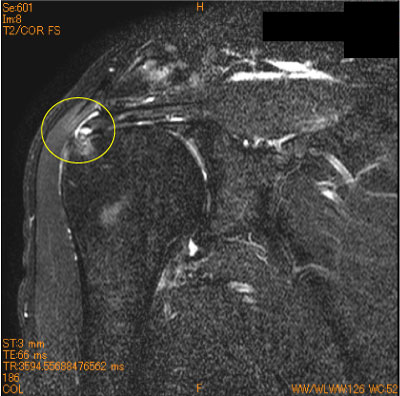

棘上筋腱停止部剥離(滑液包側部分断裂)-肩関節MRI-

60代男性、夜間痛。

棘上筋腱停止部の大結節superior facetからの剥離をみることがある。

腱自体の断裂ではないが、広義の滑液包側部分断裂に分類される。

疼痛肩では、大結節が腱板に被われていることを確認する必要がある。

![]() Obl. Cor T2WI 脂肪抑制 |